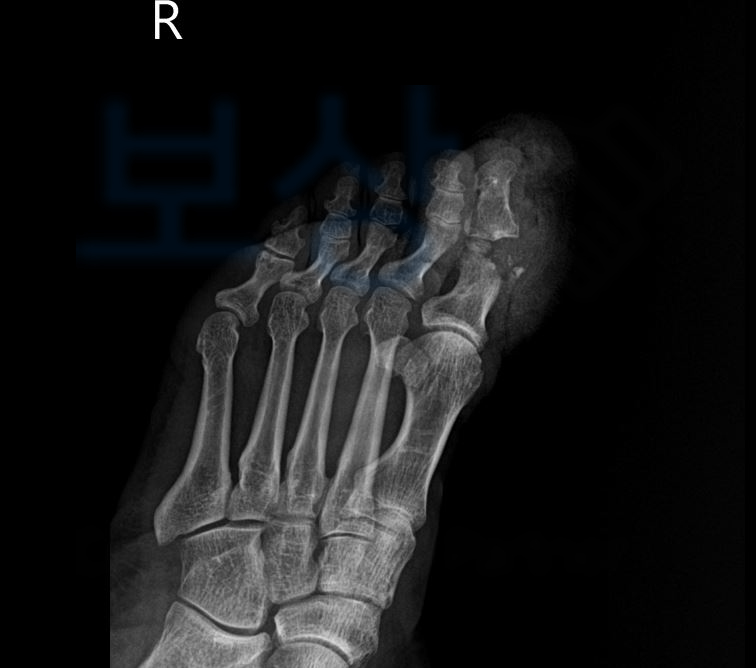

1족지 심부역상

1족지 무지신전건 파열

1족지 지간관절 골 손상 S92.41

진단을 받았고

위와 같이 골절된 파편을 모아 금속 핀으로 고정하는 수술을 받으셨습니다. 사업장에 의무적으로 가입되어 있는 산재보험을 통해 보상받으실 수 있습니다. 고@@님은 다행히 보상파트너를 만나기 전